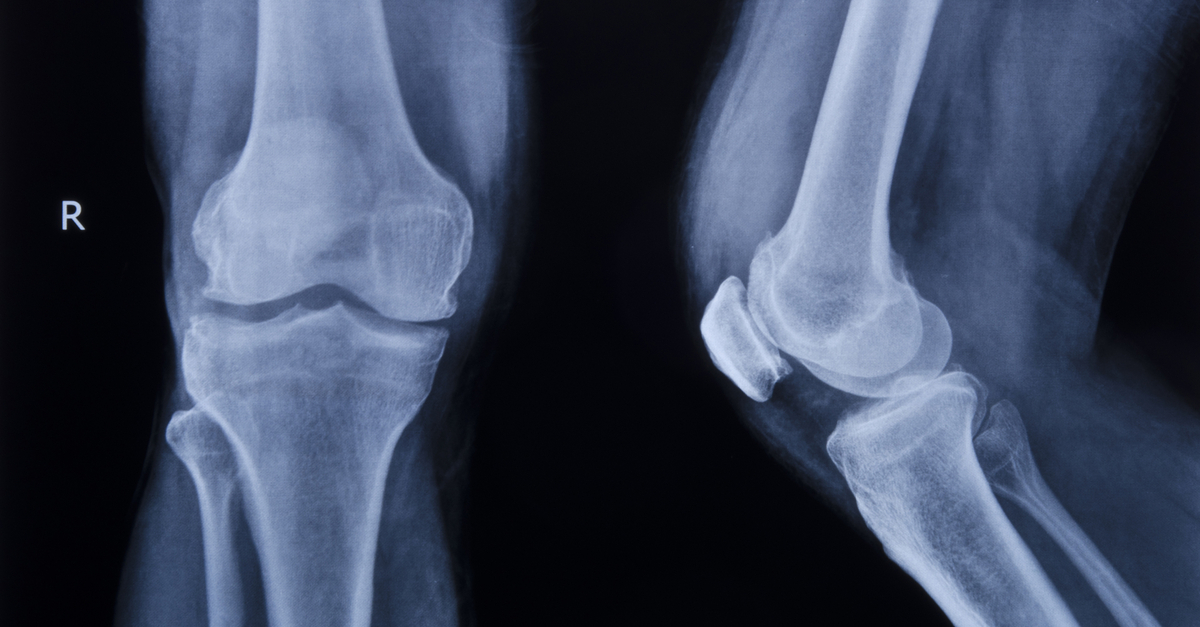

Медицинские снимки: рентген коленного сустава при остеопорозе